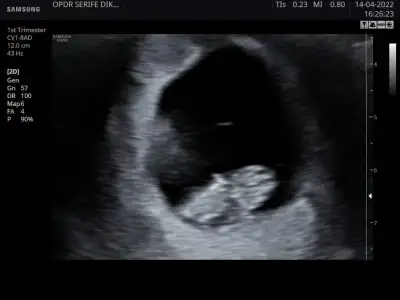

Tam 9. Haftada karından ultrason görüntüsü. Cinsiyeti ne olabilir, ben de merak ettim😊 Pasha22 Pasha22

• IMG-20220414-WA0005.webp

IMG-20220414-WA0005.webp

19,7 KB · Görüntüleme: 113